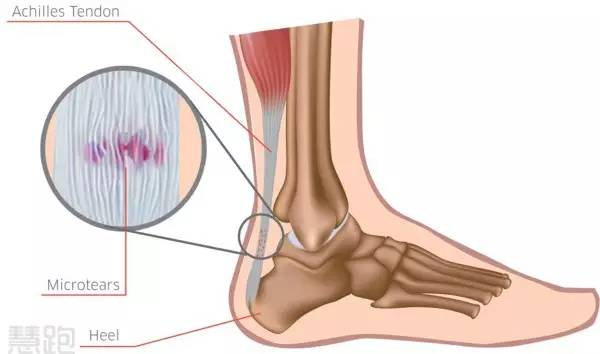

跟腱疼痛属于非常典型的过度使用损伤。在跑步过程中,跟腱要承受高达8-12倍的体重作用,也就是说跟腱受到了巨大力量的反复牵扯,导致轻微创伤反复发生,引发了跟腱力学衰竭,并随之发生结构改变,疼痛自然难以避免。

其实,跑友常常听说的“跟腱炎”这一术语并不准确。事实上跟腱局部并不存在炎症细胞,所以定义为“跟腱病”更为精准,以下均采用更为科学的术语——跟腱病。

跟腱病频繁发生在两个位置:(1)跟腱腱体上疼痛(距离跟腱止点近端2-6cm);(2)跟腱止点处疼痛。其中,跟腱腱体的疼痛比较常见。我们今天要讨论的主要是腱体疼痛,止点疼痛更为复杂。